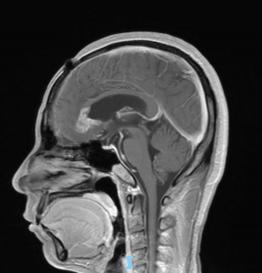

44歲的郭先生(化姓)為膠質(zhì)瘤復(fù)發(fā)患者,復(fù)查發(fā)現(xiàn)顱內(nèi)占位進(jìn)行性進(jìn)展1周,MRI檢查提示瘤體已累積到胼胝體,且瘤體位置較深,手術(shù)難度極高。面對(duì)這一挑戰(zhàn),王虎教授團(tuán)隊(duì)決定采用多種先進(jìn)技術(shù)輔助手術(shù),其中最為引人注目的就是首次引入的細(xì)胞級(jí)顯微鏡EndoSCell?。該設(shè)備是目前全球唯一實(shí)時(shí)在體細(xì)胞級(jí)顯影的儀器,可以輔助醫(yī)生從細(xì)胞層面區(qū)分腫瘤組織與正常組織,從而做到細(xì)胞級(jí)精準(zhǔn)切除。

患者術(shù)前核磁影像

整個(gè)手術(shù)過(guò)程在“腦醫(yī)匯”平臺(tái)進(jìn)行了全程直播,吸引了近千位神經(jīng)外科領(lǐng)域的專家學(xué)者觀看,他們紛紛對(duì)王虎教授團(tuán)隊(duì)的精湛技藝和EndoSCell?的先進(jìn)技術(shù)表示贊賞。術(shù)后,患者的生命體征平穩(wěn),CT及MRI檢查顯示腫瘤切除滿意,無(wú)明顯出血和并發(fā)癥。患者神志清醒,精神狀態(tài)良好,目前恢復(fù)良好。